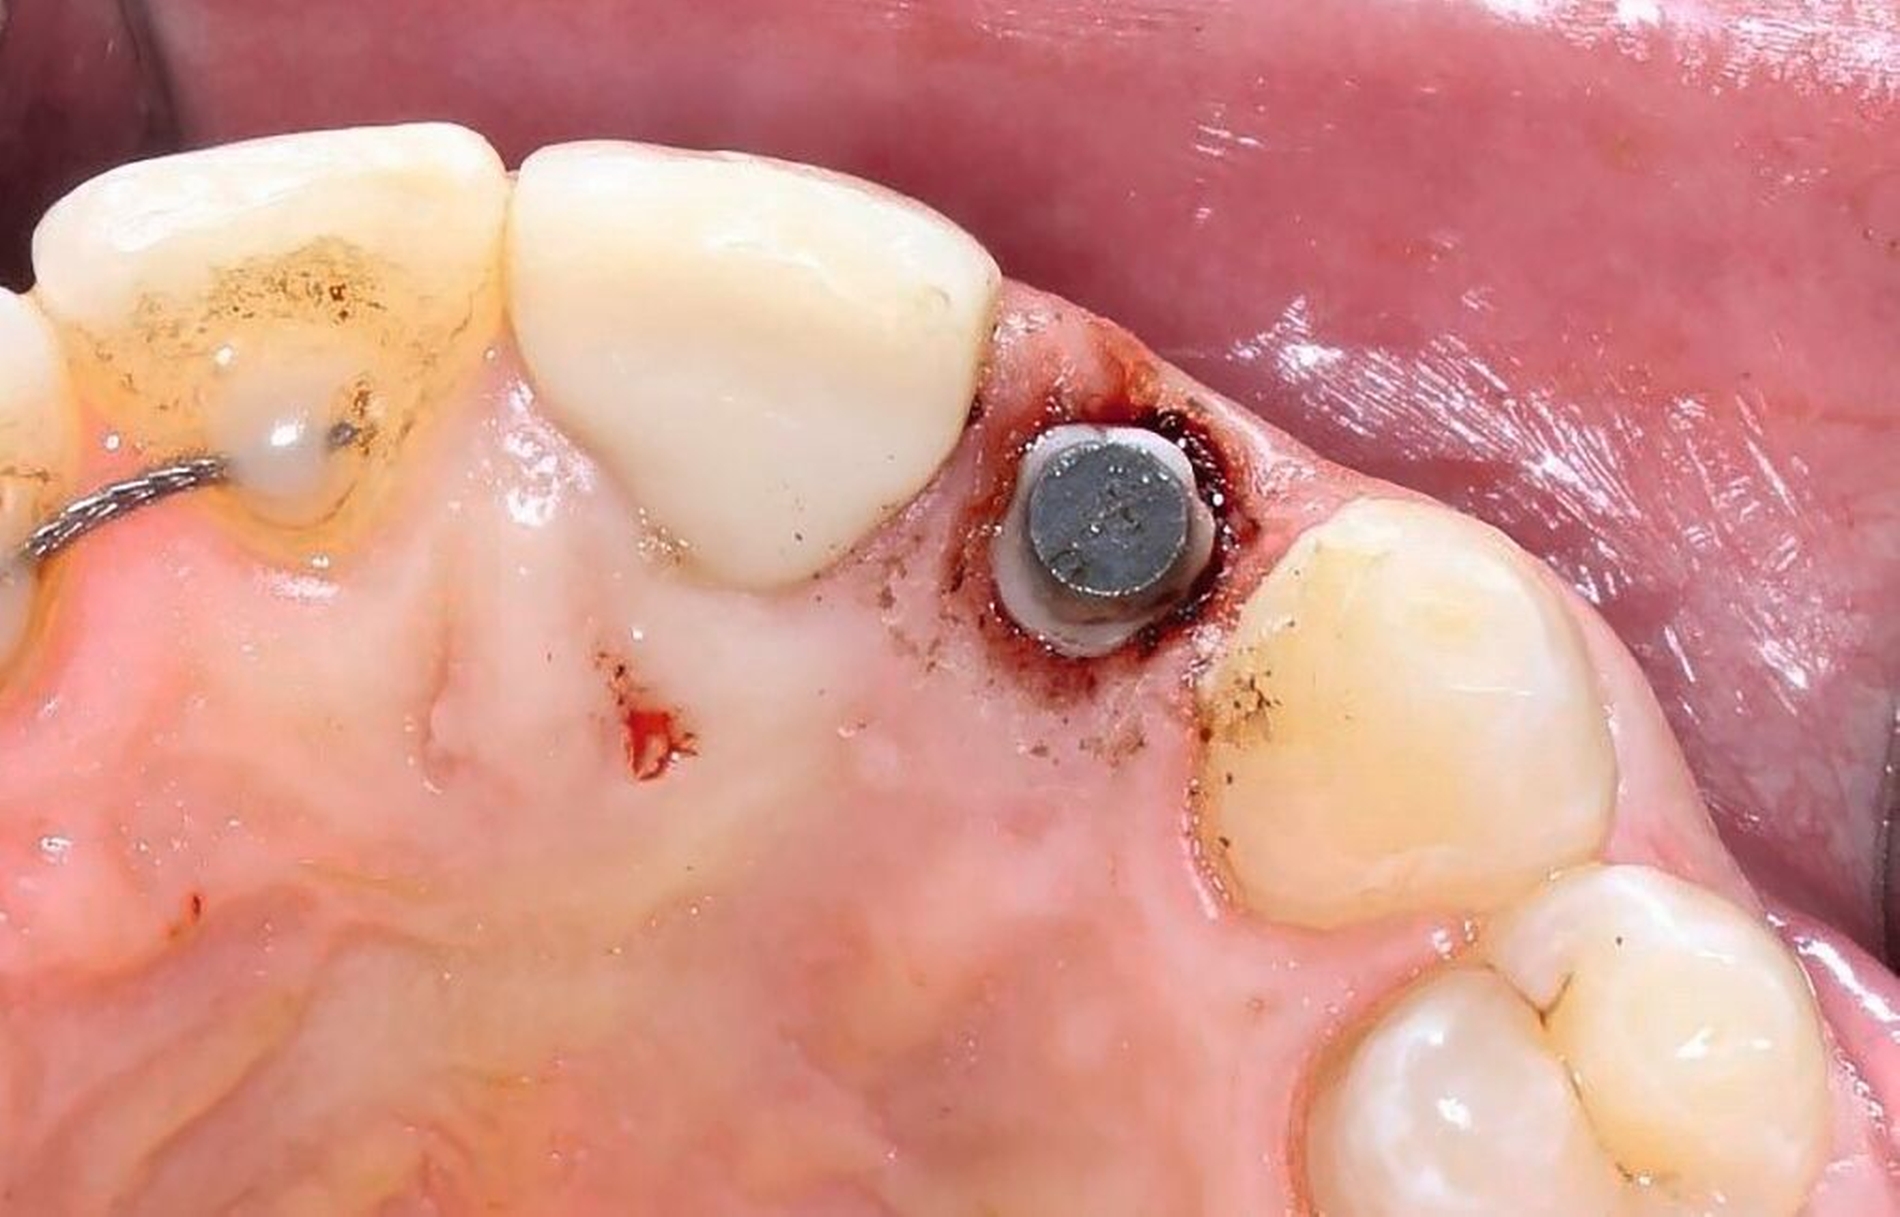

Anhand der von uns durchgeführten Einzelzahnaufnahme konnte die alio loco gestellte Erstdiagnose korrigiert werden: Wurzelfraktur des Zahnes 22 mit Kommunikation zur Mundhöhle (Abbildung 19). Der Patient favorisierte nach Diagnosesicherung zunächst Zahnersatz an 22 durch ein Sofortimplantat, weshalb eine DVT-Aufnahme zur weiteren Planung angefertigt wurde (Abbildung 20). In der Aufnahme zeigte sich jedoch, dass keine suffiziente vestibuläre Knochenlamelle vorhanden und somit der Erfolg eines Sofortimplantats nicht sicher vorhersagbar war. Nach umfassender Aufklärung entschied sich der Patient für den Zahnerhalt und eine Extrusion mit Magneten (Abbildungen 21 bis 24).

Nachdem eine Wurzelkanalbehandlung durchgeführt worden war, wurde der Magnet adhäsiv befestigt und die Zahnwurzel bis circa 4 mm über das Knochenniveau bewegt. Hierfür waren wochenweise Recalltermine notwendig, um den Magneten in der Schiene umzupositionieren und durch suprakrestale Fibrotomie die parodontalen Fasern zu lösen (Abbildung 22 und 23).